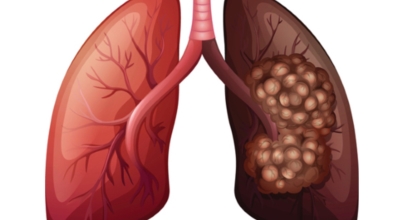

7. 폐렴 합병증: 무서운 합병증을 조심하세요!

폐렴은 치료하지 않거나 적절한 치료를 받지 못할 경우 심각한 합병증을 유발할 수 있습니다.

- 농흉: 폐를 둘러싼 흉막강에 고름이 고이는 합병증입니다. 항생제 치료와 함께 흉관 삽입술을 통해 고름을 배출해야 합니다.

- 폐농양: 폐 조직에 고름이 고이는 합병증입니다. 항생제 치료와 함께 배농 치료가 필요할 수 있습니다.

- 호흡 부전: 폐 기능 저하로 인해 혈액 내 산소 농도가 낮아지고 이산화탄소 농도가 높아지는 상태입니다. 산소 치료 또는 인공호흡기 치료가 필요할 수 있습니다.

- 패혈증: 감염이 혈액을 통해 전신으로 퍼져 발생하는 심각한 합병증입니다. 항생제 치료와 함께 수액 치료, 혈압 유지 치료 등이 필요합니다.

- 급성 호흡 곤란 증후군 (ARDS): 폐에 심한 염증이 생겨 폐 기능이 급격히 악화되는 상태입니다. 인공호흡기 치료가 필요하며, 사망률이 매우 높습니다.

- 심부전: 폐렴으로 인해 심장에 부담이 가중되어 심장 기능이 저하되는 상태입니다.